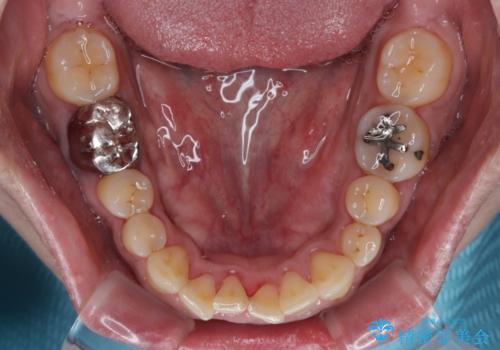

前歯の審美歯科治療 下顎の部分矯正と上顎前歯のオールセラミッククラウン

部分矯正をしたくて下顎前歯に矯正装置を付けていらっしゃいましたが、通院が難しいこともあり撤去することになりました。

痛みが消えた後に、より目立たない装置をご希望とのことで、下顎前歯の舌側矯正で部分矯正を行い、歯列が整い、上顎前歯歯根部の病変が消退したことを確認した上で、上顎前歯をオールセラミッククラウンにて補綴治療を行うこととしました。